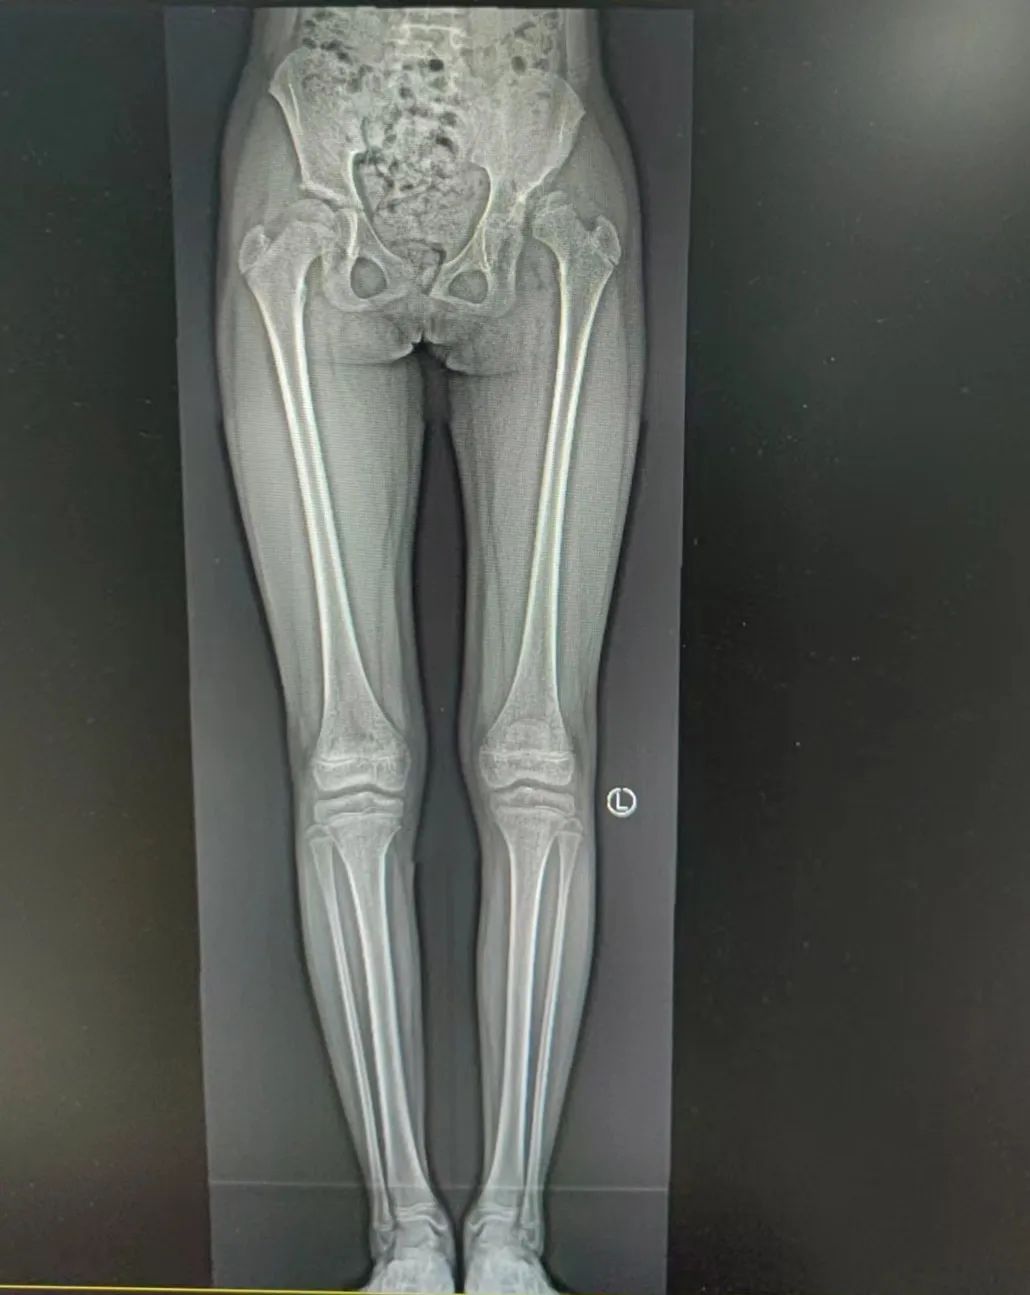

10 岁女童在 9 年前被发现左下肢跛行,一直未见好转,女童平时活动时未诉异常不适感,家长未引起重视未行治疗,随着女童年龄增大,女童觉得自己走路跛行,姿势「难看」,同时走路时出现左髋部疼痛难忍,曾到当地医院就诊,建议来江西省儿童医院治疗,骨科门诊主治医生吴敏接诊后,根据病情及检查结果,诊断女童患有「左侧发育性髋关节脱位」,经详细、耐心的解释,女童家属终于明白自己女儿得了什么病,即办理入院。

入院后完善相关检查,主任医师杜香平团队针对女童的病情进行详细讨论,为其制订了骨盆三联截骨术方案。杜香平介绍,骨盆三联截骨是目前治疗大龄儿童髋关节脱位相对有效的方法,但需要同时切断髂骨、耻骨及坐骨,其技术难度高,操作复杂,稍有不慎易损伤神经(坐骨神经、闭孔神经)和血管(存在号称死亡之冠的血管),因此手术难度对于医生来说是个不小的挑战。

经团队充分、细致的术前准备,杜香平团队,在麻醉科手术室的密切配合下进行手术。经过严密的手术操作,女童的髋臼产生足够的旋转,较充分的矫正了畸形。旋转后的髋臼中心不外移,术后步态影响较少,明显增加了女童的髋臼透明软骨承重面积。

杜香平介绍,发育性髋关节脱位是儿童常见的髋部畸形,其治疗越早,疗效越好。发育性髋关节脱位患儿由于持续负重,髋臼、股骨头的畸形病变逐渐加重,软组织也随着股骨头的逐渐上移而变形明显。大龄儿童发育性髋关节脱位(≥ 8 岁以上儿童),因其髋臼生物塑形潜力小,已形成了不可逆的骨性畸形,治疗困难,致残疾率高,对患儿及其家庭造成极大的危害。